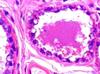

What is pictured

compound serous acini glands